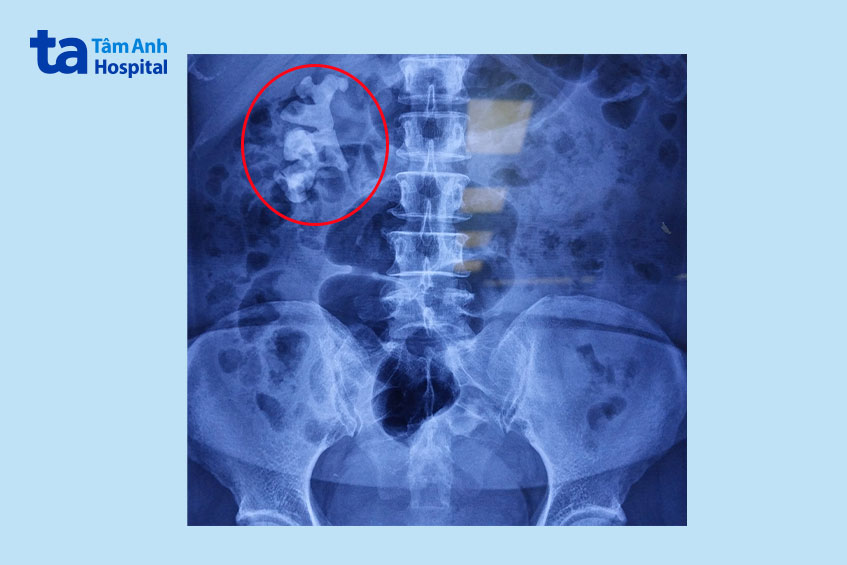

3 tháng nay, bà K.Đ.P. (59 tuổi, Đồng Nai) đau âm ỉ vùng thắt lưng bên phải. Bà đã bị sỏi thận nhiều năm, khám bác sĩ dưới quê chỉ cho bà uống thuốc. Gần đây bàn đau lưng ngày càng nhiều hơn do sỏi thận đã rất to. Khi đến khám tại Bệnh viện Đa khoa Tâm Anh TP.HCM, thạc sĩ bác sĩ Nguyễn Tân Cương, Phó khoa Tiết niệu, Trung tâm Tiết niệu – Thận học – Nam khoa, cho bà P. chụp X-quang vùng bụng, phát hiện thận phải có khối sỏi san hô nhiều nhánh đường kính khoảng 7 cm chiếm gần trọn quả thận và gần như lấp đầy bể thận và các đài thận.

Sỏi san hô là một loại sỏi đặc biệt, được hình thành và lớn dần trong thận mà nhiều người bệnh thường không nhận biết. Có hai dạng sỏi san hô: sỏi bán san hô và sỏi san hô chính danh. Ở những trường hợp thường gặp, khối sỏi được tạo thành từ những viên sỏi lớn nhỏ khác nhau, có thể có những viên nằm tách biệt nên gọi là sỏi bán san hô. Còn trường hợp bà P., sỏi san hô tạo thành một khối hoàn chỉnh.

Sỏi san hô không chỉ lấp đầy bể thận mà còn có các nhánh đi sâu vào trong các đài thận. Do thường hình thành trong môi trường nước tiểu nhiễm khuẩn nên sỏi san hô còn được gọi là sỏi nhiễm trùng. Sỏi phát triển nhanh, có thể hình thành khối lớn chỉ trong 6-12 tháng.